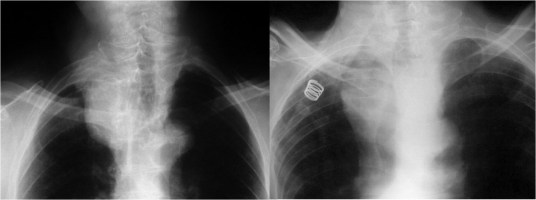

Observa estas dos imágenes que parecen similares. En ambas hay un aumento de densidad en la parte superior del contorno mediastínico derecho. Sin embargo, la de la izquierda se extiende por encima de la sombra de la clavícula, mientras que la de la izquierda acaba a la altura de ésta. En la radiografía posteroanterior de tórax, si una lesión mediastínica sobrepasa el borde superior de la clavícula, debe ser posterior, ya que el mediastino anterior no sobrepasa ese nivel. En el caso de la imagen izquierda hablamos de signo cervicotorácico positivo y en la imagen derecha de signo cervicotorácico negativo.

La imagen de la izquierda se trataba efectivamente de una lesión posterior, concretamente de una metástasis vertebral (flecha roja), mientras que la de la derecha es una elongación de troncos supraaórticos. La flecha blanca señala la arteria subclavia derecha. Esta está en contacto con el pulmón y por tanto puede verse su contorno lateral. Por encima de este plano (a la altura del borde medial de la clavícula) el vaso queda rodeado de la grasa mediastínica y por tanto su contorno desaparece (hace silueta).